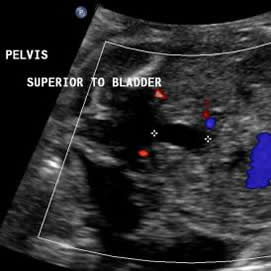

Above. Note the fetal bladder and the anechoic extension of a cyst-like structure superiorly.

Above. Urachal cyst. 23 weeks. Same patient as above showing an anechoic structure extending to the umbilicus. Color Doppler showed no flow within the cyst.